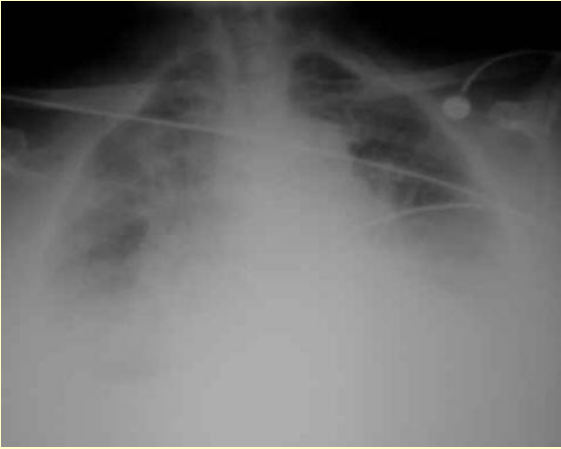

75 yo man, non-smoker, 3/7 hx of productive cough and pyrexia, RR 28, BP 90/70, HR 110 NSR, sats 84% on RA, CXR (below)

What can you see in the CXR? What would you do? What would the target sats be?

Pneumonia.

Prescribe O2 via non-rebreathe bag, ?humidified. No target sats. Do ABG, call for help!